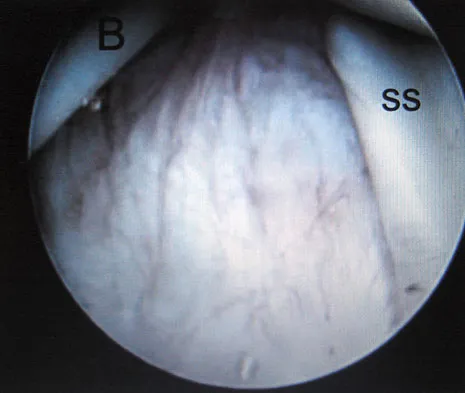

A 29-year-old woman who underwent an anterior cruciate ligament (ACL) reconstruction 6 months ago now reports difficulty achieving full knee extension, and physical therapy fails to provide relief. The knee is stable on ligament testing. Figure 3 shows the findings at a repeat arthroscopy. Treatment should now include

Figure 28 shows an arthroscopic view of a right shoulder in the lateral position through a posterior portal. What is the area between structure B (biceps) and SS (subscapularis tendon)?